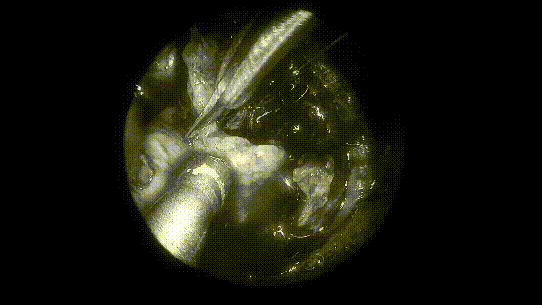

▼INC福教授术中操作步骤图解

术中操作步骤图解

将肿瘤分离出来——Basilar Artery,基底动脉;Left VA,左侧椎动脉; Right VA,右侧椎动脉;

肿瘤取出后,可见清晰的周围血管神经。R VI,右侧展神经;LVI,左侧展神经;R AICA,右侧小脑下前动脉;L AICA,左小脑下前动脉;R VA,右侧椎动脉;LVA,左侧椎动脉;Basilar ,基底